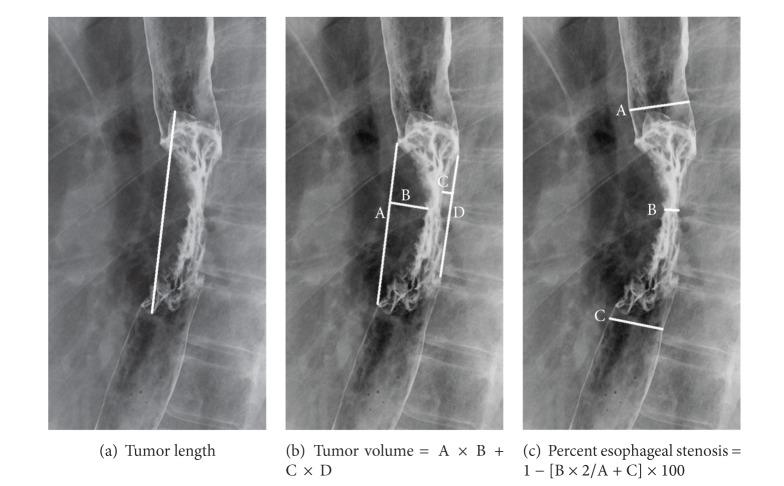

Purpose. This retrospective study examined the usefulness of barium esophagography, focusing on the luminal stenosis, in the response evaluation of neoadjuvant chemoradiotherapy (NACRT) in patients with esophageal cancer. Materials and Methods. Thirty-four patients with primary advanced esophageal cancer (≥T2) who were treated with NACRT before surgical resection were analyzed. All patients underwent barium esophagography before and after NACRT. The tumor length, volume, and percent esophageal stenosis (PES) before and after NACRT were measured. These values and their changes were compared between histopathologic responders (n = 22) and nonresponders (n = 12). Results. Posttreatment tumor length and PES in responders (4.5 cm ± 1.1 and 33.0% ± 18.5) were significantly smaller than those in nonresponders (5.8 cm ± 1.9 and 48.0% ± 12.9) (P = 0.018). Regarding posttherapeutic changes, the decrease in PES in responders (31.5% ± 13.9) was significantly greater than that in nonresponders (14.4% ± 10.7) (P < 0.001). The best decrease in PES cutoff with which to differentiate between responders and nonresponders was 18.8%, which yielded a sensitivity of 91% and a specificity of 75%. Conclusions. Decrease in PES is a good parameter to differentiate responders from nonresponders for NACRT. Barium esophagography is useful in response evaluation to NACRT in patients with locally advanced esophageal cancer.

https://cdn.ncbi.nlm.nih.gov/pmc/blobs/15a6/3867826/75d0e6efb95e/RRP2013-502690.001.jpg